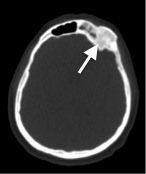

По данным КТ головного мозга, костей черепа: дополнительные образования костей черепа слева (лобной, клиновидной). КТ-признаки правостороннего гайморита в фазе отека.

- МРТ головного мозга с внутривенным контрастированием: МР-признаки полиоссальной фиброзной дисплазии (см. описание). Умеренный экзофтальм. Умеренное расширение конвекситальных субарахноидальных пространств. МР — данных за очаговые изменения вещества головного мозга не получено (рис. 13, 14).

- ПЭТ-КТ, МСКТ скелета в ЭНЦ: в левых отделах лобной кости (рис. 15), в клиновидной кости, теле и левой ветви нижней челюсти определяется расширение границ кости, уплотнение структуры по типу «матового стекла». Также визуализируются участки разряжения и уплотнения 3–6 ребер слева, грудных и поясничных позвонков, S1 позвонка. Аналогичные изменения в проксимальных отделах левой бедренной кости, теле и гребне левой подвздошной кости (рис. 16). Выявленные изменения костей соответствуют полиоссальной форме ФД.

Рис. 13. Пациентка Щ. МРТ головы: фиброзная дисплазия в левой скуловой кости.

Описание. Асимметричная деформация и утолщение костей черепа с разрастанием фиброзной ткани: скуловых костей, больше слева, с умеренной деформацией латеральной стенки левой орбиты. Глазные яблоки выстоят кпереди, задний контур расположен кзади от межскуловой линии справа на 6,4 мм, слева на 7,3 мм (норма 9,9+/-1.7 мм).

Рис. 15. Пациентка Щ. МСКТ, аксиальная плоскость. Полиоссальная форма фиброзной дисплазии. Уплотнение структуры левых отделов лобной кости и клиновидной кости.

Рис. 16. Пациентка Щ. МСКТ, криволинейная реконструкция.

Полиоссальная форма фиброзной дисплазии. Разряжение структуры костей с сохранением трабекулярного рисунка без деструкции кортикального слоя в проксимальных отделах левой бедренной кости, теле и гребне левой подвздошной кости (стрелки).